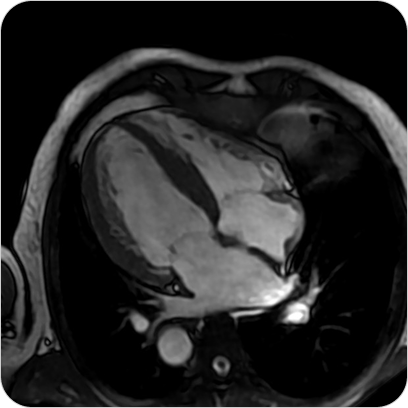

Resonancia Magnética Cardíaca

La resonancia magnética cardíaca es un estudio no invasivo y altamente especializado que permite obtener imágenes detalladas del corazón en movimiento. Brinda información precisa sobre la estructura, función, tejidos y vasos del corazón, sin utilizar radiación.

¿PARA QUE SE UTILIZA?

- Estudio de última generación para evaluar el corazón con altísima precisión, sin radiación. Diagnóstico completo de función, tejidos y circulación cardíaca.

- Evaluar la función del corazón y de las válvulas cardíacas.

Detectar infartos antiguos o recientes y analizar el daño al miocardio. - Diagnóstico de miocardiopatías (hipertrófica, dilatada, restrictiva, etc.).

- Detección de inflamación (miocarditis) o fibrosis del músculo cardíaco.

- Evaluación prequirúrgica o seguimiento de enfermedades cardíacas complejas.

- Estudio de tumores cardíacos o enfermedades congénitas.

¿POR QUÉ ES UN ESTUDIO DESTACADO?

- Estudio de última generación para evaluar el corazón con altísima precisión, sin radiación. Diagnóstico completo de función, tejidos y circulación cardíaca.

- Evaluar la función del corazón y de las válvulas cardíacas.

Detectar infartos antiguos o recientes y analizar el daño al miocardio. - Diagnóstico de miocardiopatías (hipertrófica, dilatada, restrictiva, etc.).

- Detección de inflamación (miocarditis) o fibrosis del músculo cardíaco.

- Evaluación prequirúrgica o seguimiento de enfermedades cardíacas complejas.

- Estudio de tumores cardíacos o enfermedades congénitas.

Resonancia Magnética Cardíaca

La resonancia magnética cardíaca es un estudio no invasivo y altamente especializado que permite obtener imágenes detalladas del corazón en movimiento. Brinda información precisa sobre la estructura, función, tejidos y vasos del corazón, sin utilizar radiación.

¿PARA QUE SE UTILIZA?

- Estudio de última generación para evaluar el corazón con altísima precisión, sin radiación. Diagnóstico completo de función, tejidos y circulación cardíaca.

- Evaluar la función del corazón y de las válvulas cardíacas.

Detectar infartos antiguos o recientes y analizar el daño al miocardio. - Diagnóstico de miocardiopatías (hipertrófica, dilatada, restrictiva, etc.).

- Detección de inflamación (miocarditis) o fibrosis del músculo cardíaco.

- Evaluación prequirúrgica o seguimiento de enfermedades cardíacas complejas.

- Estudio de tumores cardíacos o enfermedades congénitas.

¿POR QUÉ ES UN ESTUDIO DESTACADO?

- Estudio de última generación para evaluar el corazón con altísima precisión, sin radiación. Diagnóstico completo de función, tejidos y circulación cardíaca.

- Evaluar la función del corazón y de las válvulas cardíacas.

Detectar infartos antiguos o recientes y analizar el daño al miocardio. - Diagnóstico de miocardiopatías (hipertrófica, dilatada, restrictiva, etc.).

- Detección de inflamación (miocarditis) o fibrosis del músculo cardíaco.

- Evaluación prequirúrgica o seguimiento de enfermedades cardíacas complejas.

- Estudio de tumores cardíacos o enfermedades congénitas.